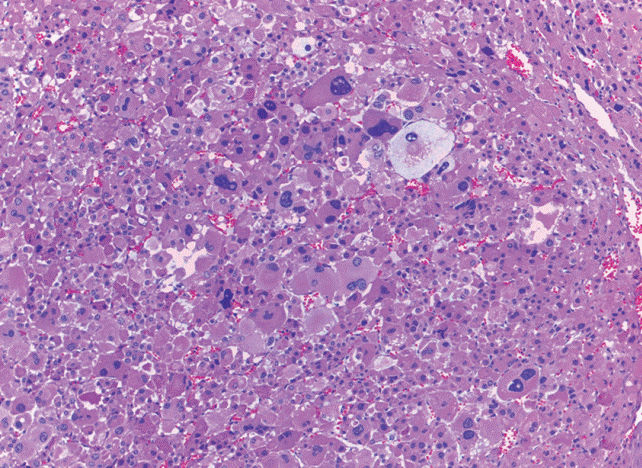

El tumor pesó 30 gramos y midió 5 × 4 × 4 cm. En la cápsula se identificaron vasos delgados visibles (Figura 1). Al corte, el tumor se apreciaba multinodular de consistencia blanda y color blanco grisáceo con áreas amarilla naranja (Figura 2). Microscópicamente, el tumor estaba constituido por células grandes con acentuado pleomorfismo y abundante citoplasma eosinófilo (Figura 3). La neoplasia comprime la corteza suprarrenal por debajo de la cápsula (Figura 4). A mayor aumento es más evidente el pleomorfismo y desde el punto de vista arquitectural el patrón es difuso (Figura 5). Hay mitosis atípicas (Figura 6) y se encuentran más de 5 mitosis por 50 campos de gran aumento. La necrosis presente como áreas eosinófilas en patrón geográfico se identifican en varios de los campos microscópicos (Figura 7). La permeación vascular es uno de los principales criterios de malignidad en los carcinomas de corteza suprarrenal; en la siguiente imagen se ilustra un vaso con un gran agregado tumoral en su luz (Figura 8). Por inmunohistoquímica se encontró un importante índice de proliferación celular, con un Ki67 de 20% que se expresa como positividad nuclear (Figura 9). La proteína p53 igualmente se expresa en forma nuclear en una proporción del 30% (Figura 10). Los criterios histopatológicos de Weiss para caracterizar neoplasias adrenocorticales malignas se ilustran en el Cuadro 2. El tumor que presentamos reúne 7 de los 9 criterios (*).

Figura 3 Microscópicamente se observan células grandes con acentuado pleomorfismo y abundante citoplasma eosinófilo.